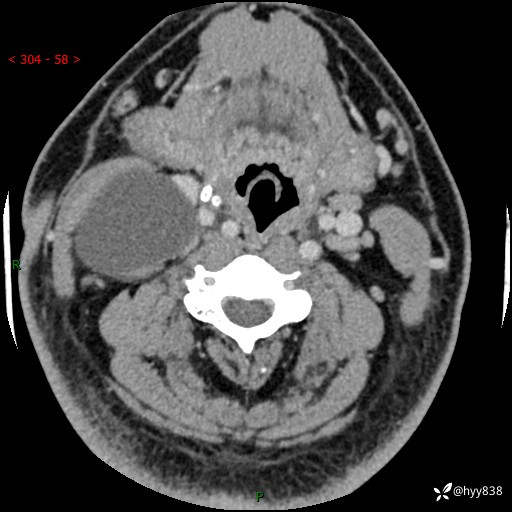

颈部CT平扫+增强